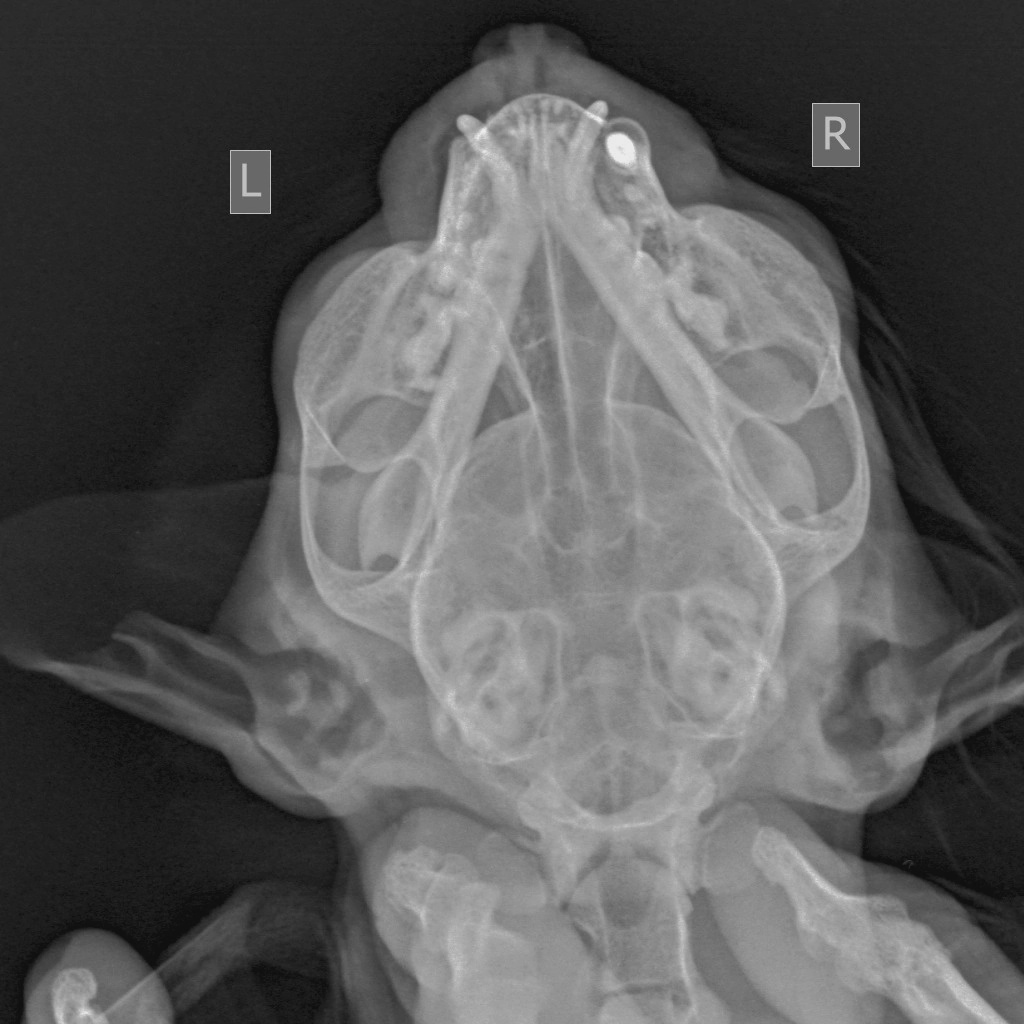

Все долго ждали новостей о кошечке Нэро ведь ей должны были сделать операцию уже, но на стационаре волонтеров в ЦВМ ее не оставили... Кошечка Нэро: пока что наша девочка будет сидеть отдельно от других хвостиков Кошечка Нэро была прооперирована в клинике Зооцентр. Операция ринотамия прошла успешно. Сейчас находится на послеоперационном стационаре там, ей колят обезболивающие препараты, кровеостанавливающие и антибиотики. Сегодня покушала самостоятельно. Мурчит, ластится. Образцы тканей отправлены на гистологическое исследование на предмет онкологического воспаления. По результатам будет назначена дальнейшая схема лечения.

Кошечка Нэро была прооперирована в клинике Зооцентр. Операция ринотамия прошла успешно. Сейчас находится на послеоперационном стационаре там, ей колят обезболивающие препараты, кровеостанавливающие и антибиотики.

Образцы тканей отправлены на гистологическое исследование на предмет онкологического воспаления.

По результатам будет назначена дальнейшая схема лечения.